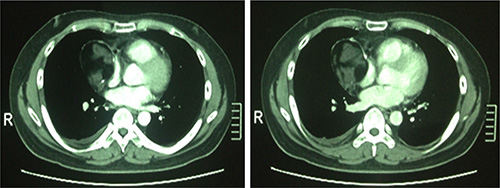

A previously healthy 25-year-old Chinese man presented to local hospital with complaint of gradually progressive heaviness of chest for three months. There were no associated signs of superior vena cava syndrome, no lymphadenopathy, and no abnormalities on genital examination. His routine hemogram, urine and blood biochemical analyses were within normal ranges. Contrast-enhanced computed tomography (CT) scan (Figure 1) of the chest showed a well-circumscribed 6 × 5 centimeters (cm), cystic and solid mass lesion in the right portion of the superior mediastinum with right pleural effusion. The capsule wall of the tumor was almost uniformly thick. The right lung parenchyma and vena cava were both compressed. No radiologic signs of invasion into the surrounding structures were present. There was no evidence of an eventual primary tumor elsewhere. Among serologic tumor markers, human epididymis protein 4 (HE4), squamous cell carcinoma associated antigen (SCC), carbohydrate antigen 19–9 (CA 19–9), cytokeratin 19 fragment (CYFRA 21–1), and neuron specific enolase (NSE) levels were within acceptable limits, but carbohydrate antigen 72–4 (CA 72–4) level was 36.56 U/ml (normal range [NR]: 0–6.9 U/ml) and carcinoembryonic antigen (CEA) level was 20.42 ng/ml (NR: 0–5.2 ng/ml). Otherwise his medical history was unremarkable.

Figure 1: The original chest computed tomography of the patient. The CT showed a well-circumscribed cystic and solid mass lesion in the right portion of the superior mediastinum measuring 6 × 5 cm with right pleural effusion.